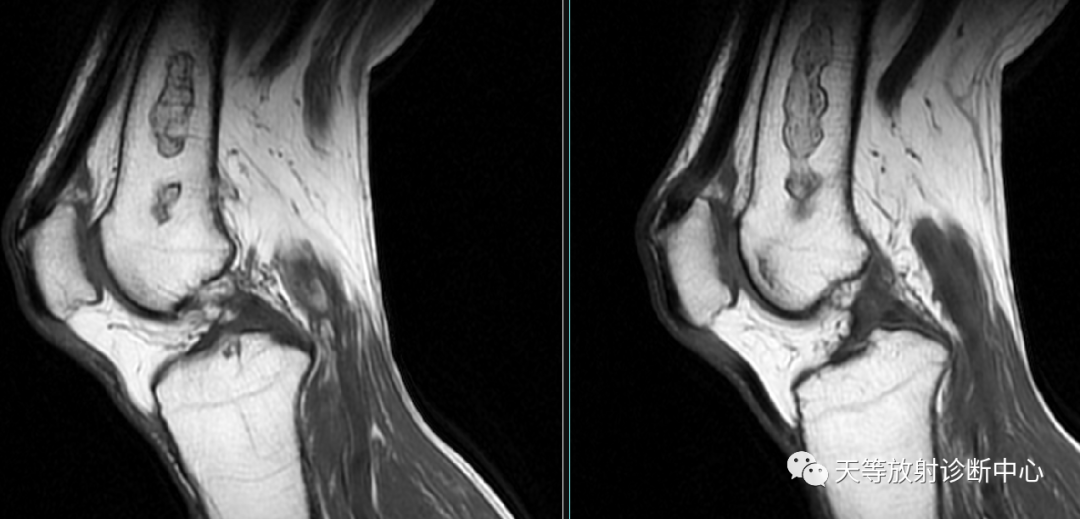

双边征,内缘高信号,外缘低信号,地图样改变

地图样改变,周围不规则线状样影包绕,关节软骨保持正常。邹月芬:骨梗死的影像学表现。

地图样改变,周围不规则线状样影包绕

典型征象是病灶边缘呈“三环征”,由外向内,T1WI呈低-高-低,压脂T2WI 高-低-高。